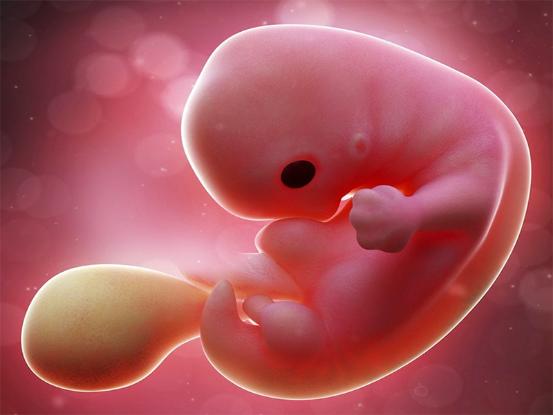

胎芽

什么是胎芽(胚芽)-有喜网

图片尺寸762x545